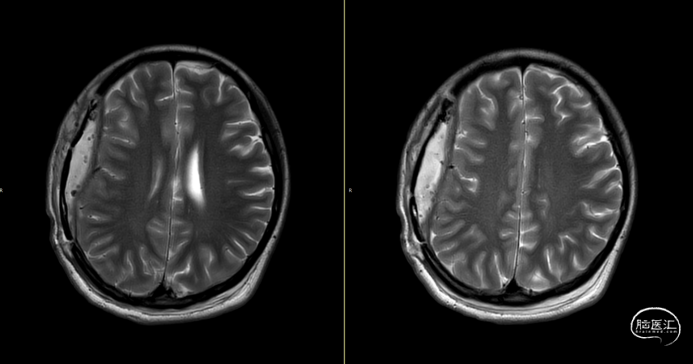

第2次术后12天,仍有间断头痛,刀口愈合可,复查颅脑MRI(如上图):右侧额顶颞部软组织稍增厚,右侧额顶部颅板下见条片状长T1、长T2信号,T2FLAIR呈稍高信号,边界清,DWI(b=1000)呈混杂高信号,相应ADC呈混杂高信号影,加用美罗培南联合万古霉素抗炎治疗。

第3次术后16天,复查颅脑MRI(如上图),硬膜外及皮下异常信号较前明显减少,负压引流管引流不明显,拔除负压引流管,继续使用头孢曲松+多西环素口服联合抗炎治疗。